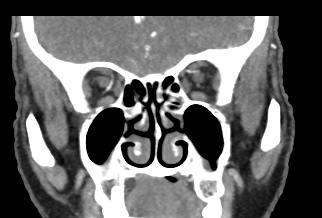

Околоносовые пазухи носа (синусы) представляют собой воздухоносные полости в костях лицевого и мозгового черепа, расположенные в непосредственной близости к полости носа. К околоносовым пазухам относят гайморовы пазухи (расположены в верхних челюстях), фронтальные синусы (в лобных костях черепа), клиновидная пазуха и ячейки решетчатого лабиринта.

Полости синусов изнутри выстланы слизистой оболочкой, они сообщаются с полостью носа, участвуют в очищении и согревании вдыхаемого воздуха и влияют на особенности тембра голоса. Околоносовые пазухи наиболее часто подвержены развитию острых и хронических воспалений, а также возникновению опухолевых образований, травматических повреждений и аномалий развития.

Мультиспиральная компьютерная томография дает информацию о состоянии полости носа, носовой перегородки, степени воздушности околоносовых пазух, путей дренирования синусов, состоянии слезных каналов. Сканирование позволяет оценить толщину слизистой, наличие патологического содержимого в просвете пазух (уровня «жидкости»), выявить опухолевые образования. С помощью КТ можно провести точную диагностику травматических повреждений костей лицевого черепа, определить локализацию инородных тел, попавших в полости синусов.

С помощью объемной реконструкции можно перед оперативным вмешательством увидеть особенности анатомии ЛОР-органов, определить точное расположение патологического очага по отношению к окружающим тканям. Компьютерная томография помогает в диагностике аномалий развития придаточных пазух носа, слезоотводящих каналов.